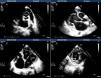

A 24-year-old black man presented to the emergency department of our hospital with fatigue and dyspnea at rest of two weeks duration. The transthoracic echocardiogram (Figure 1) revealed aneurysm of the right sinus of Valsalva (Figure 1A) dissecting into the interventricular septum (arrow) (Figure 1B), dilated left ventricle with moderately to severely impaired systolic function, and echocardiographic criteria for left ventricular non-compaction (Figure 1C and D). A submitral aneurysm and a dilated left atrium were also observed (Figure 1C). Doppler echocardiography showed mild mitral and aortic regurgitation. Multislice computed tomography with contrast (Figure 2) revealed an aneurysm of the right sinus of Valsalva (Figure 2A) dissecting into the interventricular septum (arrow) (Figure 2B), as well as a submitral aneurysm (Figure 2C) and non-compaction of the left ventricle (Figure 2D), confirming the echocardiographic findings. The patient was admitted to the cardiac intensive care unit of our hospital and treated with diuretics, angiotensin-converting enzyme inhibitors and digitalis, with dramatic improvement in symptoms. He was proposed for surgery but refused and was discharged in New York Heart Association class I. The patient died one year after the first admission.